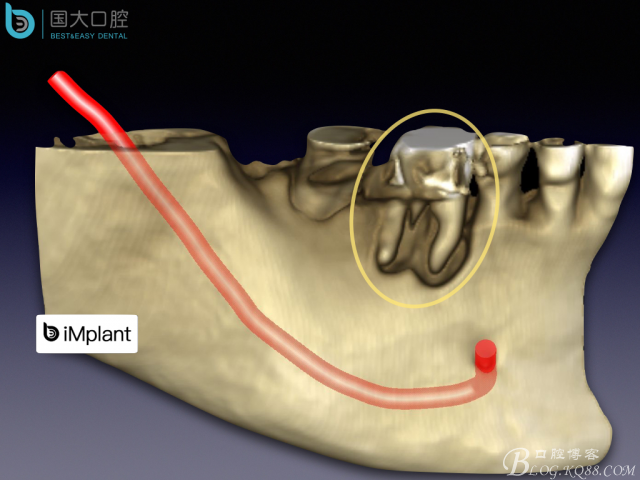

頰側(cè)骨壁嚴(yán)重缺失,應(yīng)該如何設(shè)計種植位點?

來源于國大口腔 邵現(xiàn)紅醫(yī)生發(fā)表的博文